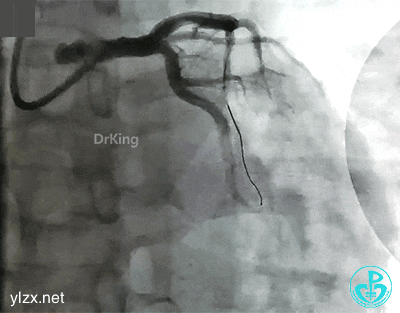

抽吸导管反复抽吸无效,前降支近端血栓无明显改变。送入Guidezilla,进入血栓部位,10ml注射器反复抽吸,抽出了类似脂肪组织样的物质。

抽吸后前降支近段血栓消失,局部残留狭窄50%。患者胸痛缓解,拟择期复查造影。